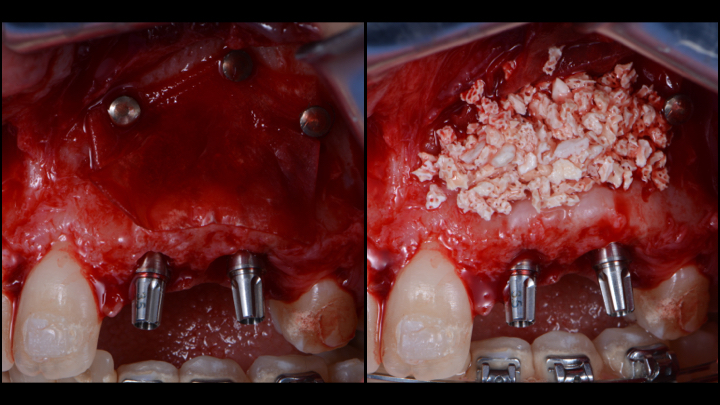

botiss cerabone® & Jason® membrane for horizontal augmentation - Clinical case by Dr. M. Steigmann

Three implants placed in a narrow posterior mandible